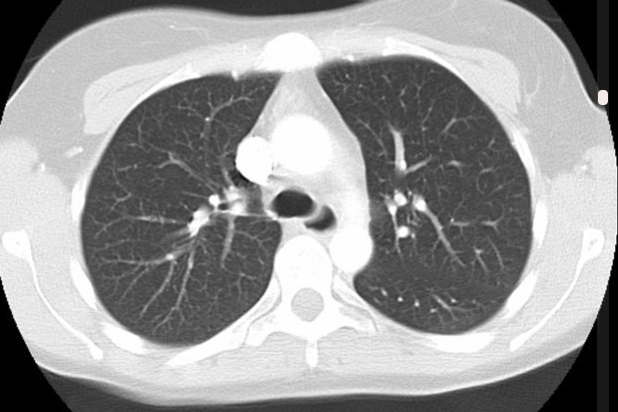

The CD Lab Machine Learning Driven Precision Imaging  (Start 2021) develops machine learning models for the prediciton of individual disease course and treatment response in lung cancer patients. It explores methodology, medicine and the legal aspects of using AI in clinical care. It is funded by the Christian Doppler Gesellschaft.

ONSET (Start 2021) is developing machine learning techniques for the detection of novel emerging diseases and the training of prediction models from early scarse observational data during a pandemic outbreak. It is part of a a collaboration with IAEA/ZODIAC, and funded by the FWF.

RIFTAIR is a registry study to collect imaging data and relevant clinical data of patients with infectious lung diseases who have undergone CT examinations. Data collection includes data from before the ongoing COVID-19 pandemic, and continues as a prospective study.

PULMARCH - Computerized 3D Pulmonary Architecture Analysis, funded by the Austrian Science Fund FWF, (2010 - 2014) The goal of this project is to create a computer-aided diagnosis (CAD) system to differentiate between the textural expression of usual interstitial pneumonia (UIP, the histopathological counterpart of IPF) and NSIP, while providing increased sensitivity/specificity over today's differential diagnosis.